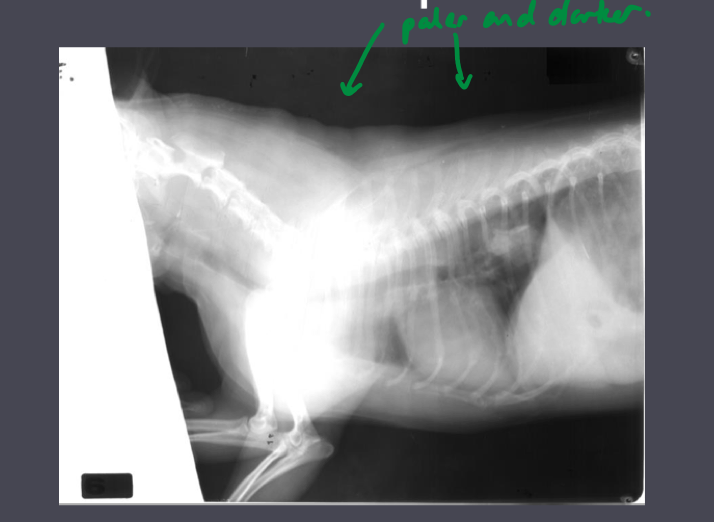

What is the issue with the developement of this film?

This film has been underdeveloped. Low image density and poor detail. Poor contrast. The background also has very poor density